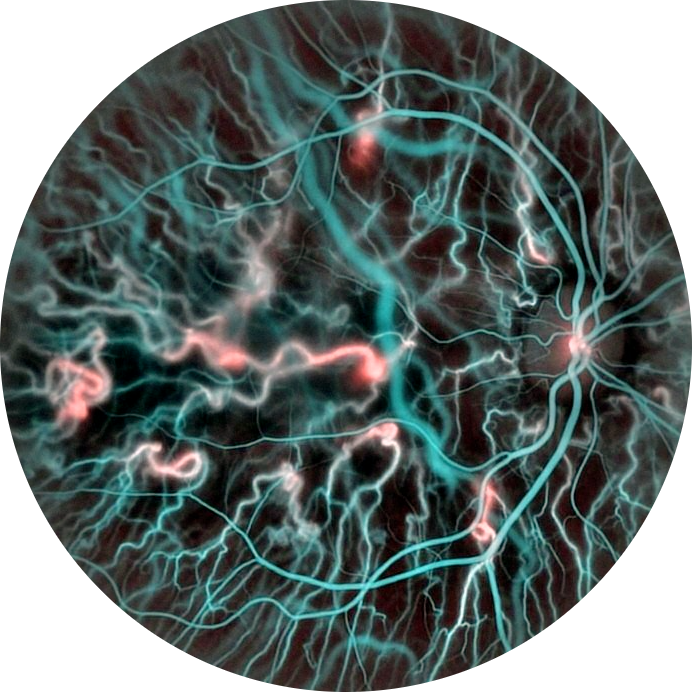

Deep-learning segmentation of vascular structure from HoloDoppler results.

DopplerView produces enhanced vascular maps, supports artery-vein discrimination, and prepares clean, analysis-ready inputs for downstream EyeFlow quantification.

DopplerView is the segmentation layer of the open-source Doppler holography ecosystem.

It turns HoloDoppler renderings into consistent vascular representations that can be used directly by EyeFlow for quantitative retinal hemodynamics.

Built for fast, reproducible preparation of vascular masks and topology-aware image enhancement in retinal blood-flow imaging.

The goal is to reduce manual intervention, improve anatomical consistency, and make quantitative workflows more robust across datasets and operators.